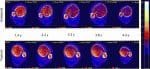

Les données ont montré que le patient effectuaient environ 8000 contractions par mois. Un système permettait l’intervention de l’équipe soignante lorsque l’observance au traitement diminuait. Le couple développé par le soléaire et l’index de fatigue ont augmenté avec l’entrainement. La DMO du tibia "non entrainé" a diminué de 14% environ par an contre une diminution de 7% pour le tibia dont le soléaire était stimulé. C’est la corticale postérieure du tibia qui a été la mieux préservée.